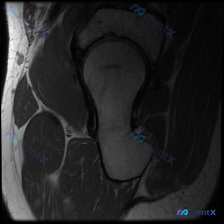

看到一个髋关节MRI病例,先给大家分享一下核心发现: 影像类型:髋关节MRI冠状位T1加权成像 主要表现:股骨头及股骨颈近端骨髓呈弥漫性T1低信号,与正常脂肪骨髓的高信号形成鲜明对比;髋臼顶轮廓清晰,关节间隙无明显狭窄,盂唇在T1序列上未见明确撕裂征象。 患者主诉提到了“盂唇病变”,但影像核心是骨髓...